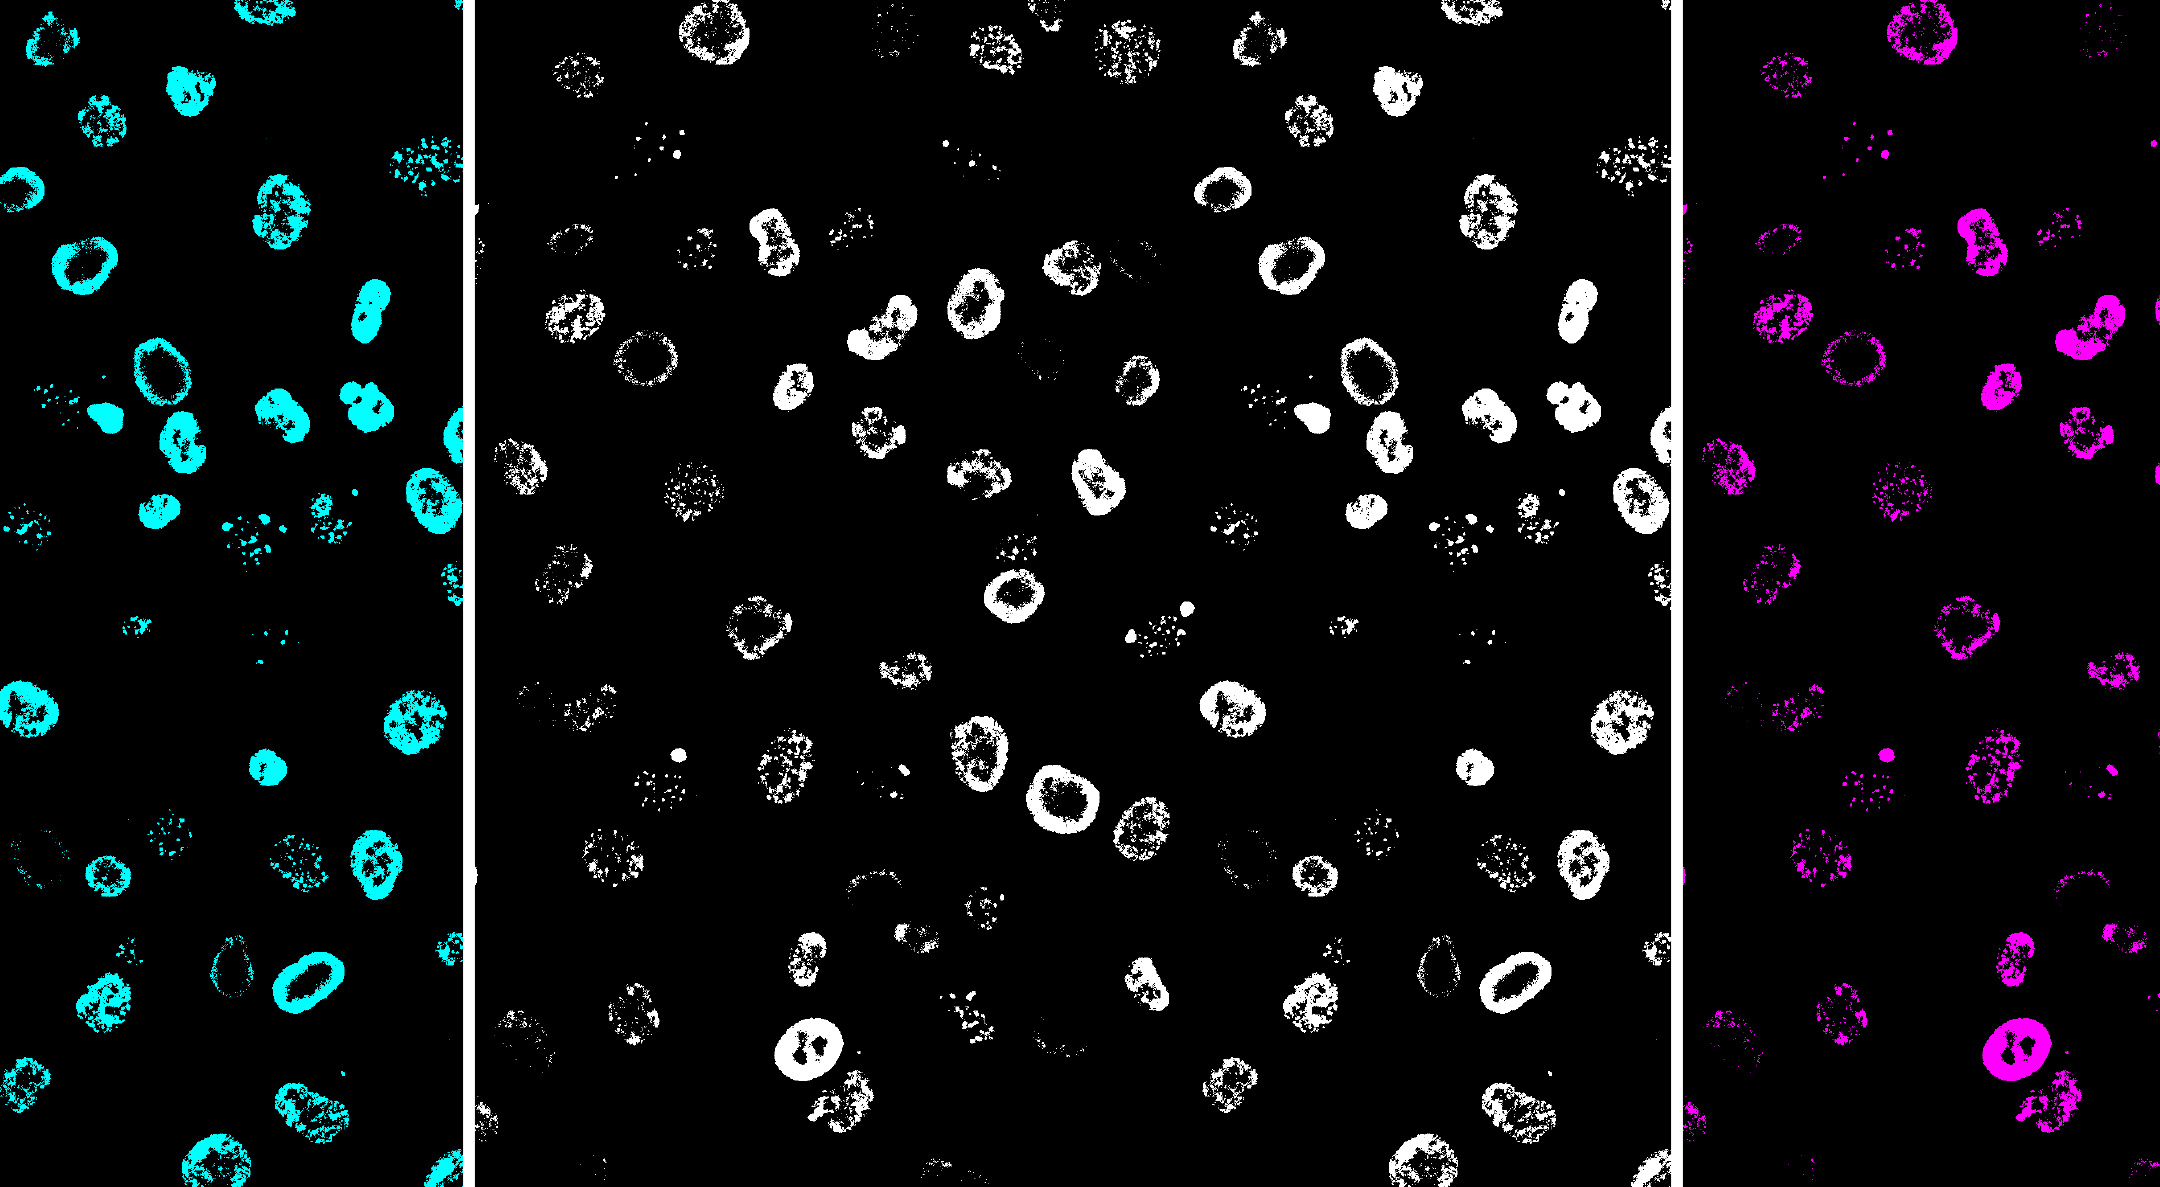

’I’ve noticed something unusual with the typhoid toxin’. These were the words of my then PhD student, Angela Ibler, in November 2016 just weeks after moving our laboratory to our new home at the University of Sheffield. ‘I’ve been playing with the microscopes here at the Wolfson Light Microscopy Facility. Have a look at these images…’. I take a look and instantly know we’re onto something: ‘What on earth are those rings?’. These images kick-started our journey unravelling a non-canonical DNA damage response induced by the typhoid toxin of Salmonella Typhi, which we call the RING phenotype, for obvious reasons, just check out the images showing cells with donut-shaped rings of DNA damage.

Fig: RINGs of DNA damage in human cells caused by the typhoid toxin underlying typhoid fever